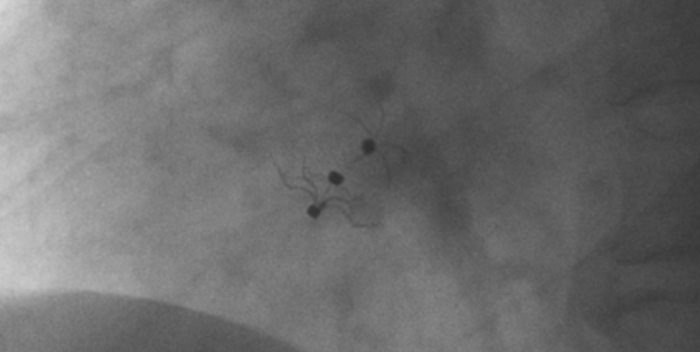

造影顯示長(zhǎng)隧道型PFO